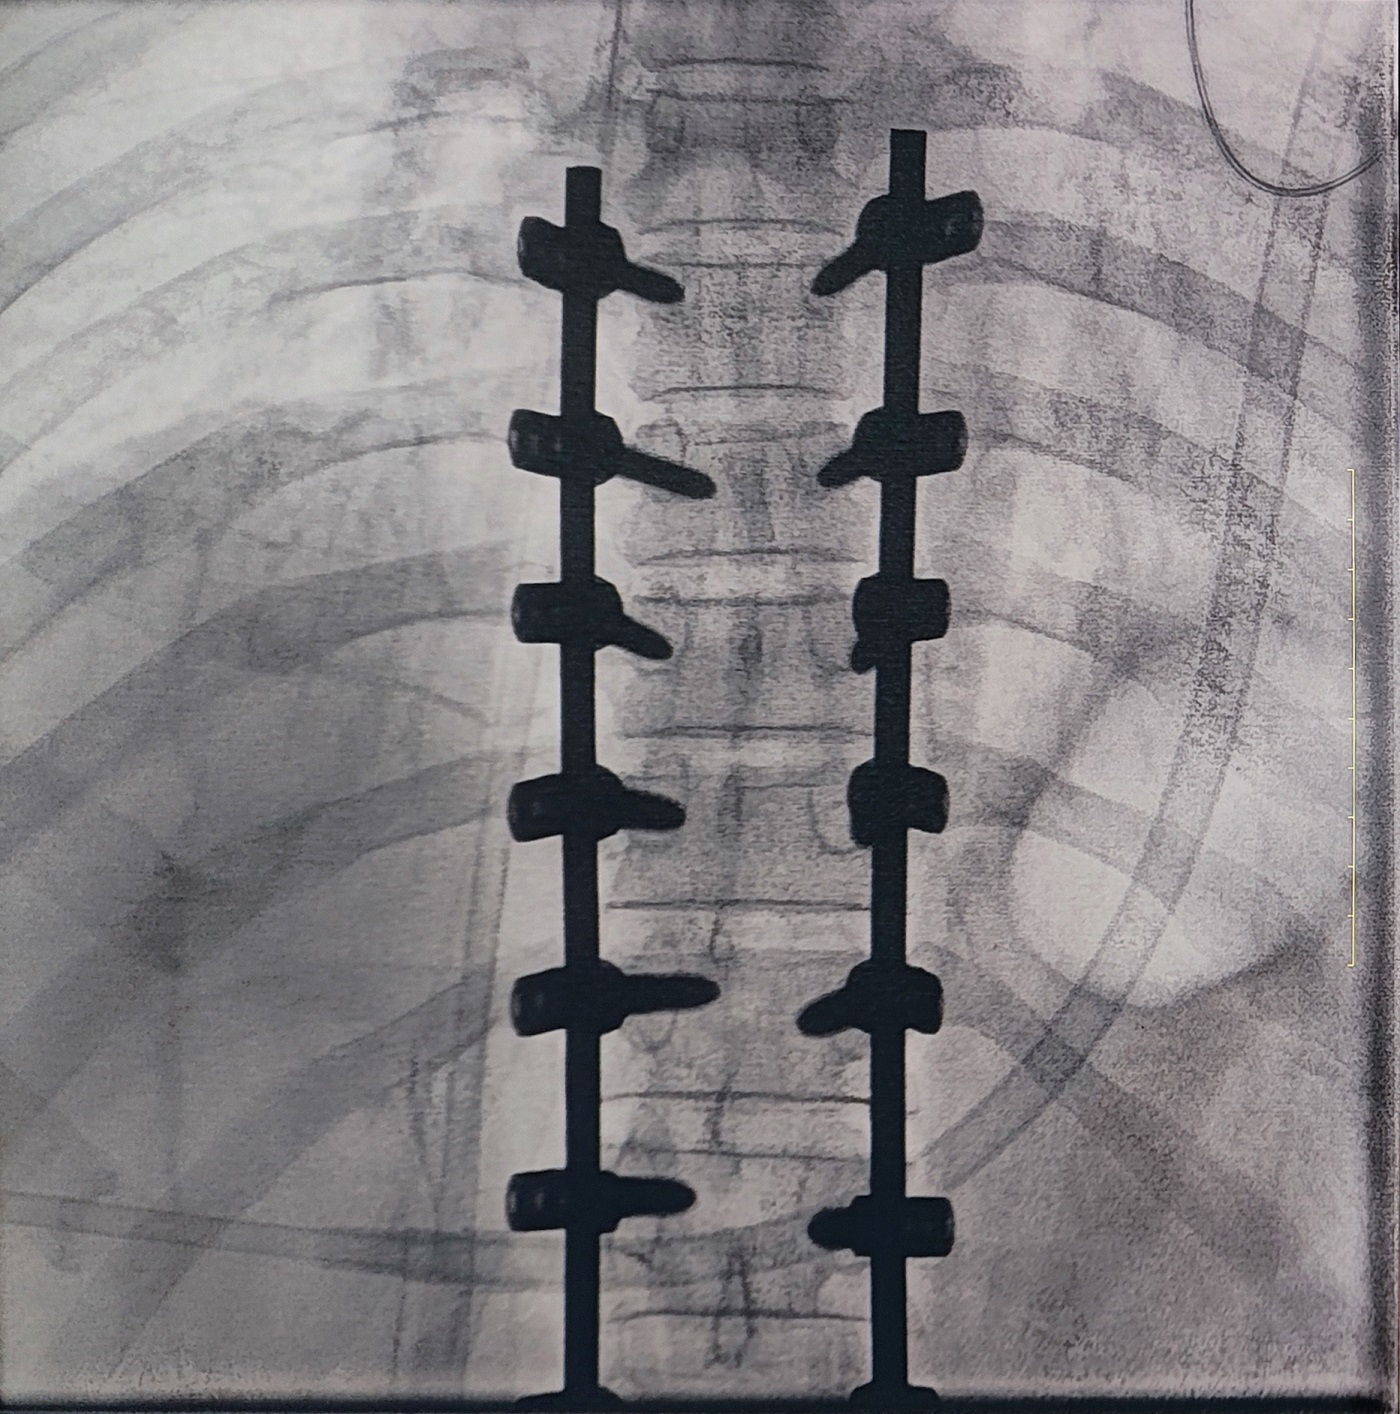

一場(chǎng)脊柱手術(shù)中,醫(yī)生需要拍攝跨越7個(gè)節(jié)段的脊柱影像,由于曝光的視野較大,常規(guī)視野的C形臂通常需要拍攝2-3次,普愛(ài)醫(yī)療大平板一體式C形臂30CM*30CM的“大視野”,輔助醫(yī)生一次性完成了7個(gè)節(jié)段的拍攝。最終,醫(yī)生在高清影像的輔助下完成了14枚螺釘?shù)木珳?zhǔn)定位、置入。

大視野,不僅意味著醫(yī)生可以更快,獲取更全面的影像信息,做出精準(zhǔn)判斷,無(wú)需多次拍攝定位,也顯著地降低了患者接受的輻射劑量,保護(hù)了患者的安全。